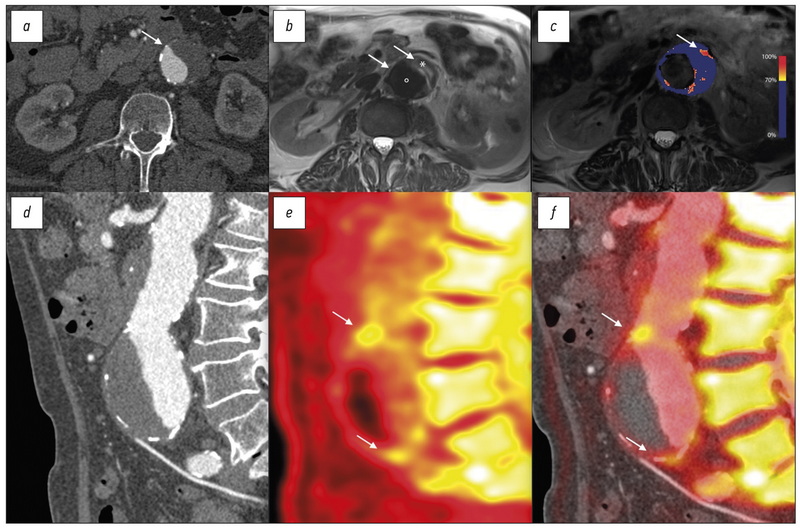

- Vesey AT, Jenkins WS, Irkle A, et al. 18F-Fluoride and 18F-fluorodeoxyglucose positron emission tomography after transient ischemic attack or minor ischemic stroke: Case-Control study. Circ Cardiovasc Imaging. 2017;10(3):e004976. doi: 10.1161/CIRCIMAGING.116.004976

- Joshi NV, Vesey AT, Williams MC, et al. 18F-fluoride positron emission tomography for identification of ruptured and high-risk coronary atherosclerotic plaques: a prospective clinical trial. Lancet. 2014; 383(9918):705–713. doi: 10.1016/S0140-6736(13)61754-7

- Forsythe RO, Dweck MR, McBride OM, et al. 18F–Sodium fluoride uptake in abdominal aortic aneurysms: the SoFIA3 study. J Am Coll Cardiol. 2018;71(5):513–523. doi: 10.1016/j.jacc.2017.11.053

- Derlin T, Tóth Z, Papp L, et al. Correlation of inflammation assessed by 18F-FDG PET, active mineral deposition assessed by 18F-fluoride PET, and vascular calcification in atherosclerotic plaque: a dual-tracer PET/CT study. J Nucl Med. 2011;52(7):1020–1027. doi: 10.2967/jnumed.111.087452